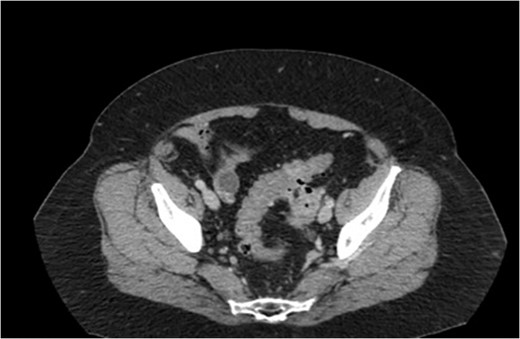

A transvaginal ultrasound, obtained by the patient’s gynecologist, showed a linear hyperechoic structure within the fundal portion of the endometrial canal. The suspicion was that of a retained intrauterine device. In addition, there was a right-sided avascular complex cyst measuring 2.5 × 2.2 × 1.8 cm3. A CT scan of the pelvis was then obtained. The CT scan, highlighted in Figs 1 and 2, revealed multiple foci of gas within the left ovary and fistulization of the adjacent sigmoid colon with questionable air in the fallopian tube.